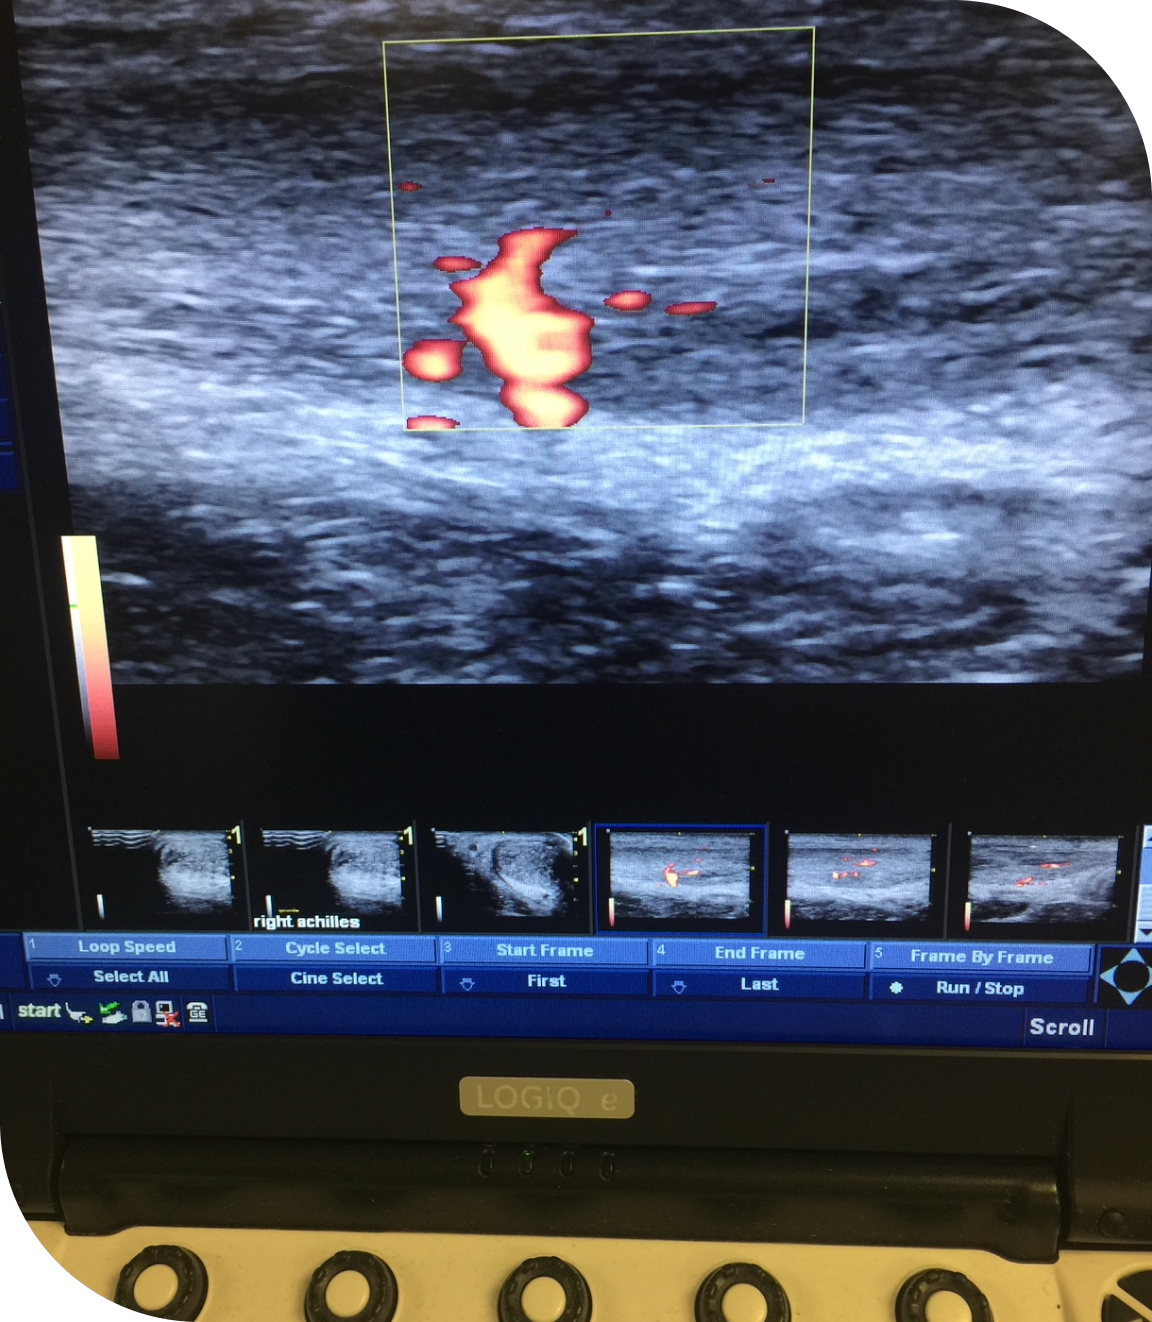

Dr. Clarke Holmes offers musculoskeletal ultrasound (MSK ultrasound) as part of his advanced diagnostic andtreatment services. This non-invasive imaging allows for real-time evaluation of soft tissue injuries and joint conditions. MSK ultrasound is used to assess concerns including joint inflammation, ligament sprains and tears, muscle strains, bursitis, and tendon injuries like rotator cuff, tennis and golfer’s elbow or Achilles tendon/plantar fascia issues.

MSK ultrasound is an excellent tool in sports medicine and orthopedics, offering real-time imaging that allows us to see muscles, tendons, ligaments, and joints in motion. This helps us identify the exact source of pain or injury in your body. It also enables guided injections, improving accuracy and comfort during procedures. Ultrasound-guided injections also produce greater benefit than blind (landmark-based) injections.

• Ankle and Foot (Achilles, posterior tibial and peroneal tendonitis; plantar fasciitis)